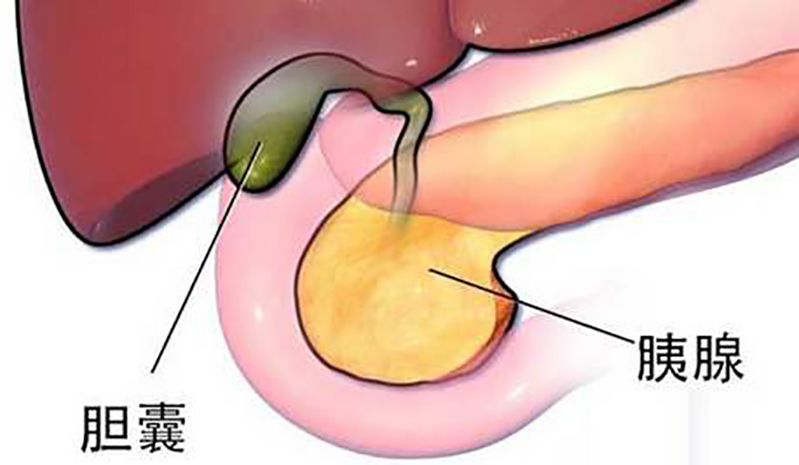

胆囊息肉应该称为胆囊息肉样病变,是胆囊黏膜向胆囊腔内局限性隆起的病变。随着健康体检的广泛普及以及腹部超声的广泛应用,胆囊息肉样病变检出率日益增高。对于突然而来的......